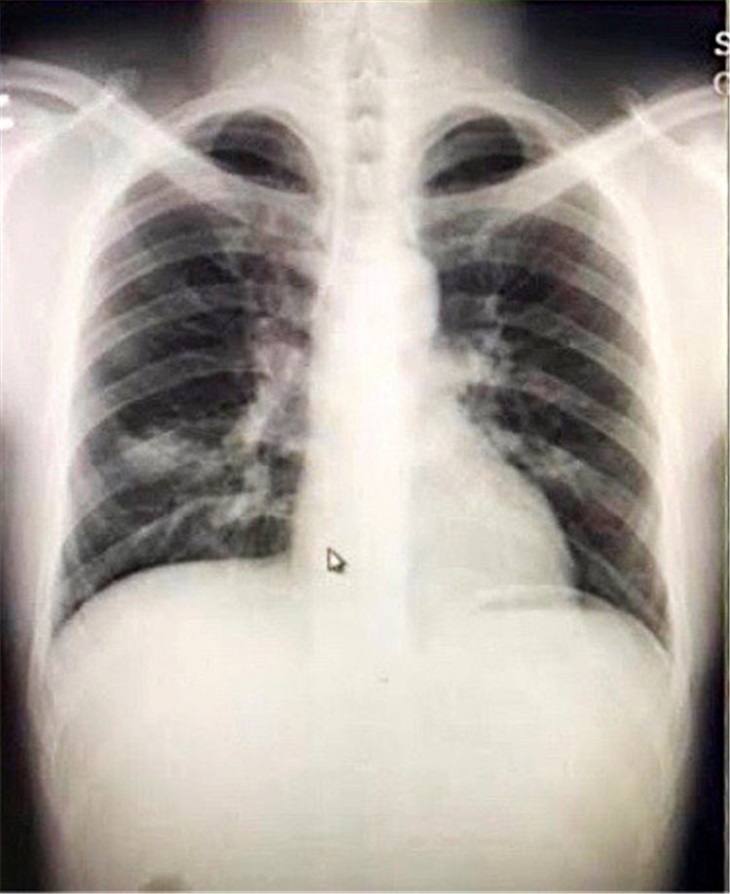

- Bệnh nhân viêm phổi do 2019-nCoV tại Việt Nam: bệnh nhân nam 65 tuổi có bệnh nền tăng huyết áp, tiểu đường, bệnh động mạch vành, hình ảnh X quang khi nhập viện có đám mờ ranh giới không rõ vùng giữa và đỉnh phổi trái, ranh giới không rõ. Sau 3 ngày các đám mờ khu trú, ranh giới rõ ở phổi trái [11].

Hình ảnh bệnh nhân nhập viện (đông đặc thùy trên phổi trái) (A) và sau 3 ngày (đông đặc phổi trái lan rộng hơn) (B) [11]